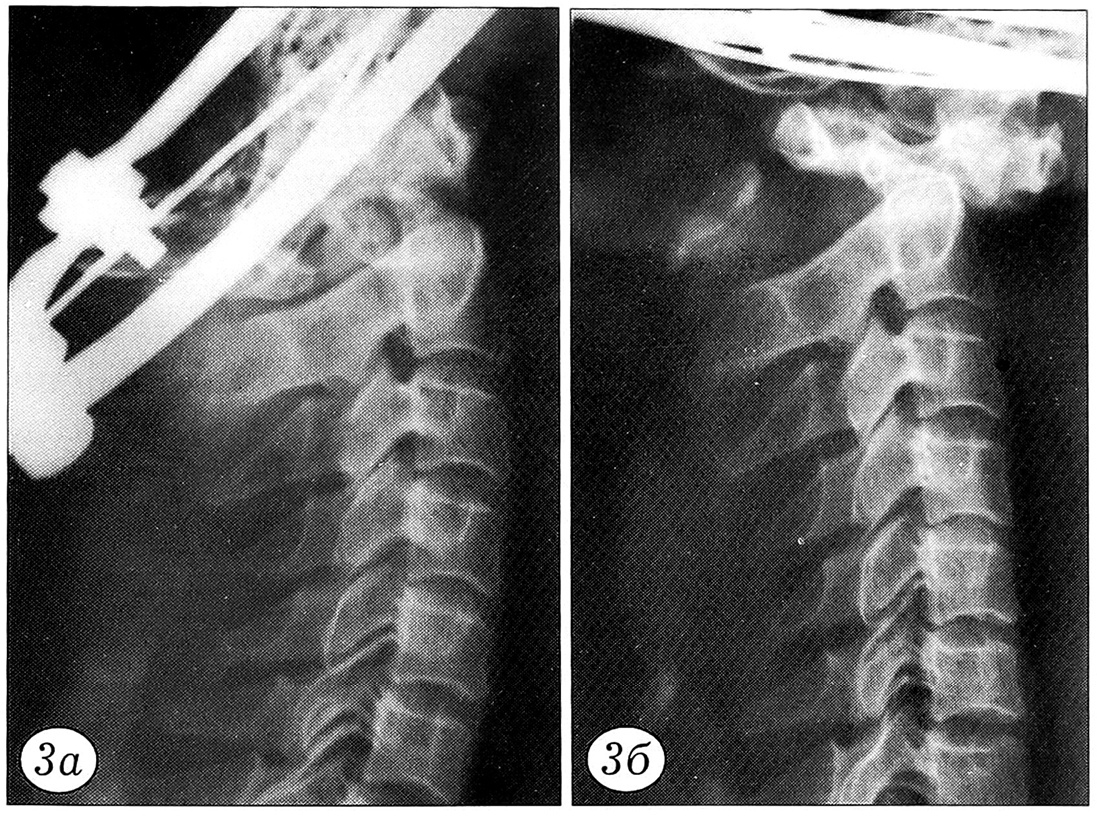

Результаты нагрузочного теста документировались графически. По оси ординат регистрировалось усилие в ньютонах, по оси абцисс — степень смещения позвонков в миллиметрах (рис. 2). При этом основное внимание уделялось величине нагрузки, при которой происходило наибольшее смещение позвонков. До и после нагрузочного теста производилась рентгенография блоков (рис. 3~5).

Рис. 3. Перелом зубовидного отростка С2 позвонка типа 2 до (а) и после (б) нагрузочного теста.